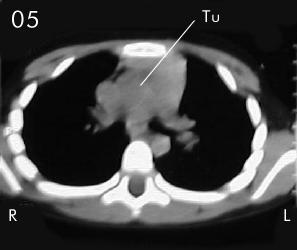

Tomografía torácica

Estudio Tomográfico tórax completo: En detalles los cortes progresivos desde el manubrio esternal hasta 2 cm sub carinal traqueal. (vistas desde el abdomen), (R) = derecho , (L) = Izquierdo; no se apreciaron procesos en pleura ni parenquima pulmonar.

En Mediastino antero superior:

Corte 05 y Corte 06: extensión peritraqueal y subcarinal de la lesión, bien limitada sin infiltración de estructuras vecinas.